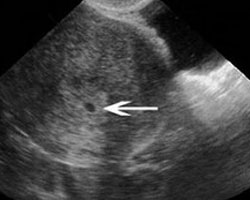

Continua o caminho para a fecundação. Oferecemos-te a imagem de uma ecografia de duas semanas, para que possas ter uma ideia do que se poderia observar, neste caso a bolsa gestacional.

Ecografia de duas semanas